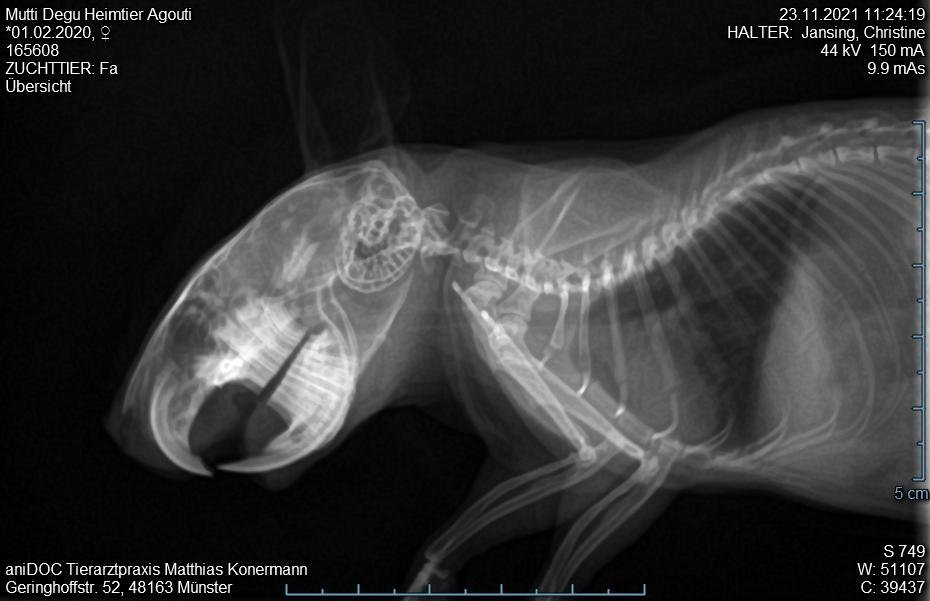

3. Tierarztbesuch am 23.11. Tier merklich mitgenommen, laute Atmung, nun auch beim Abhören der Lunge. Gewichtsverlust etwa 25-30 g. Sehr schwere Flankenatmung. Röntgenbild unter Gasnarkose. Tierarzt sieht nix drauf, Zähne sind aber gut. Verdacht auf Bauchfellentzündung. Neues AB borgal/riketron 24%, 2 Mal täglich 0.5 ml. Dachte, das Tier überlebt die Nacht nicht. Aber Verbesserung seit dem 25.11. Tier frisst wieder, ist bei 189g.